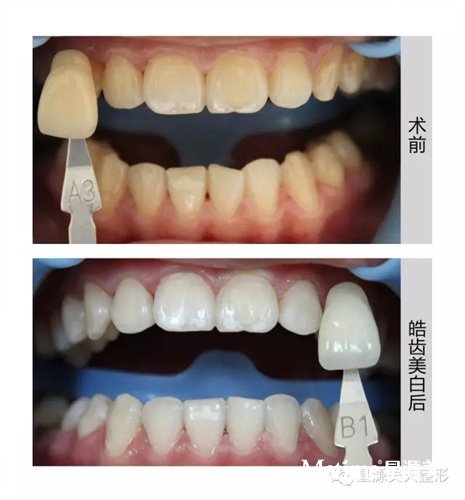

从牙齿美白、贴面、修复到正畸、隐适美隐形矫正...,胡谦主任带给顾客的不仅是一口漂亮的牙齿,更是对内心自信的提升。

皓齿美白前后对比